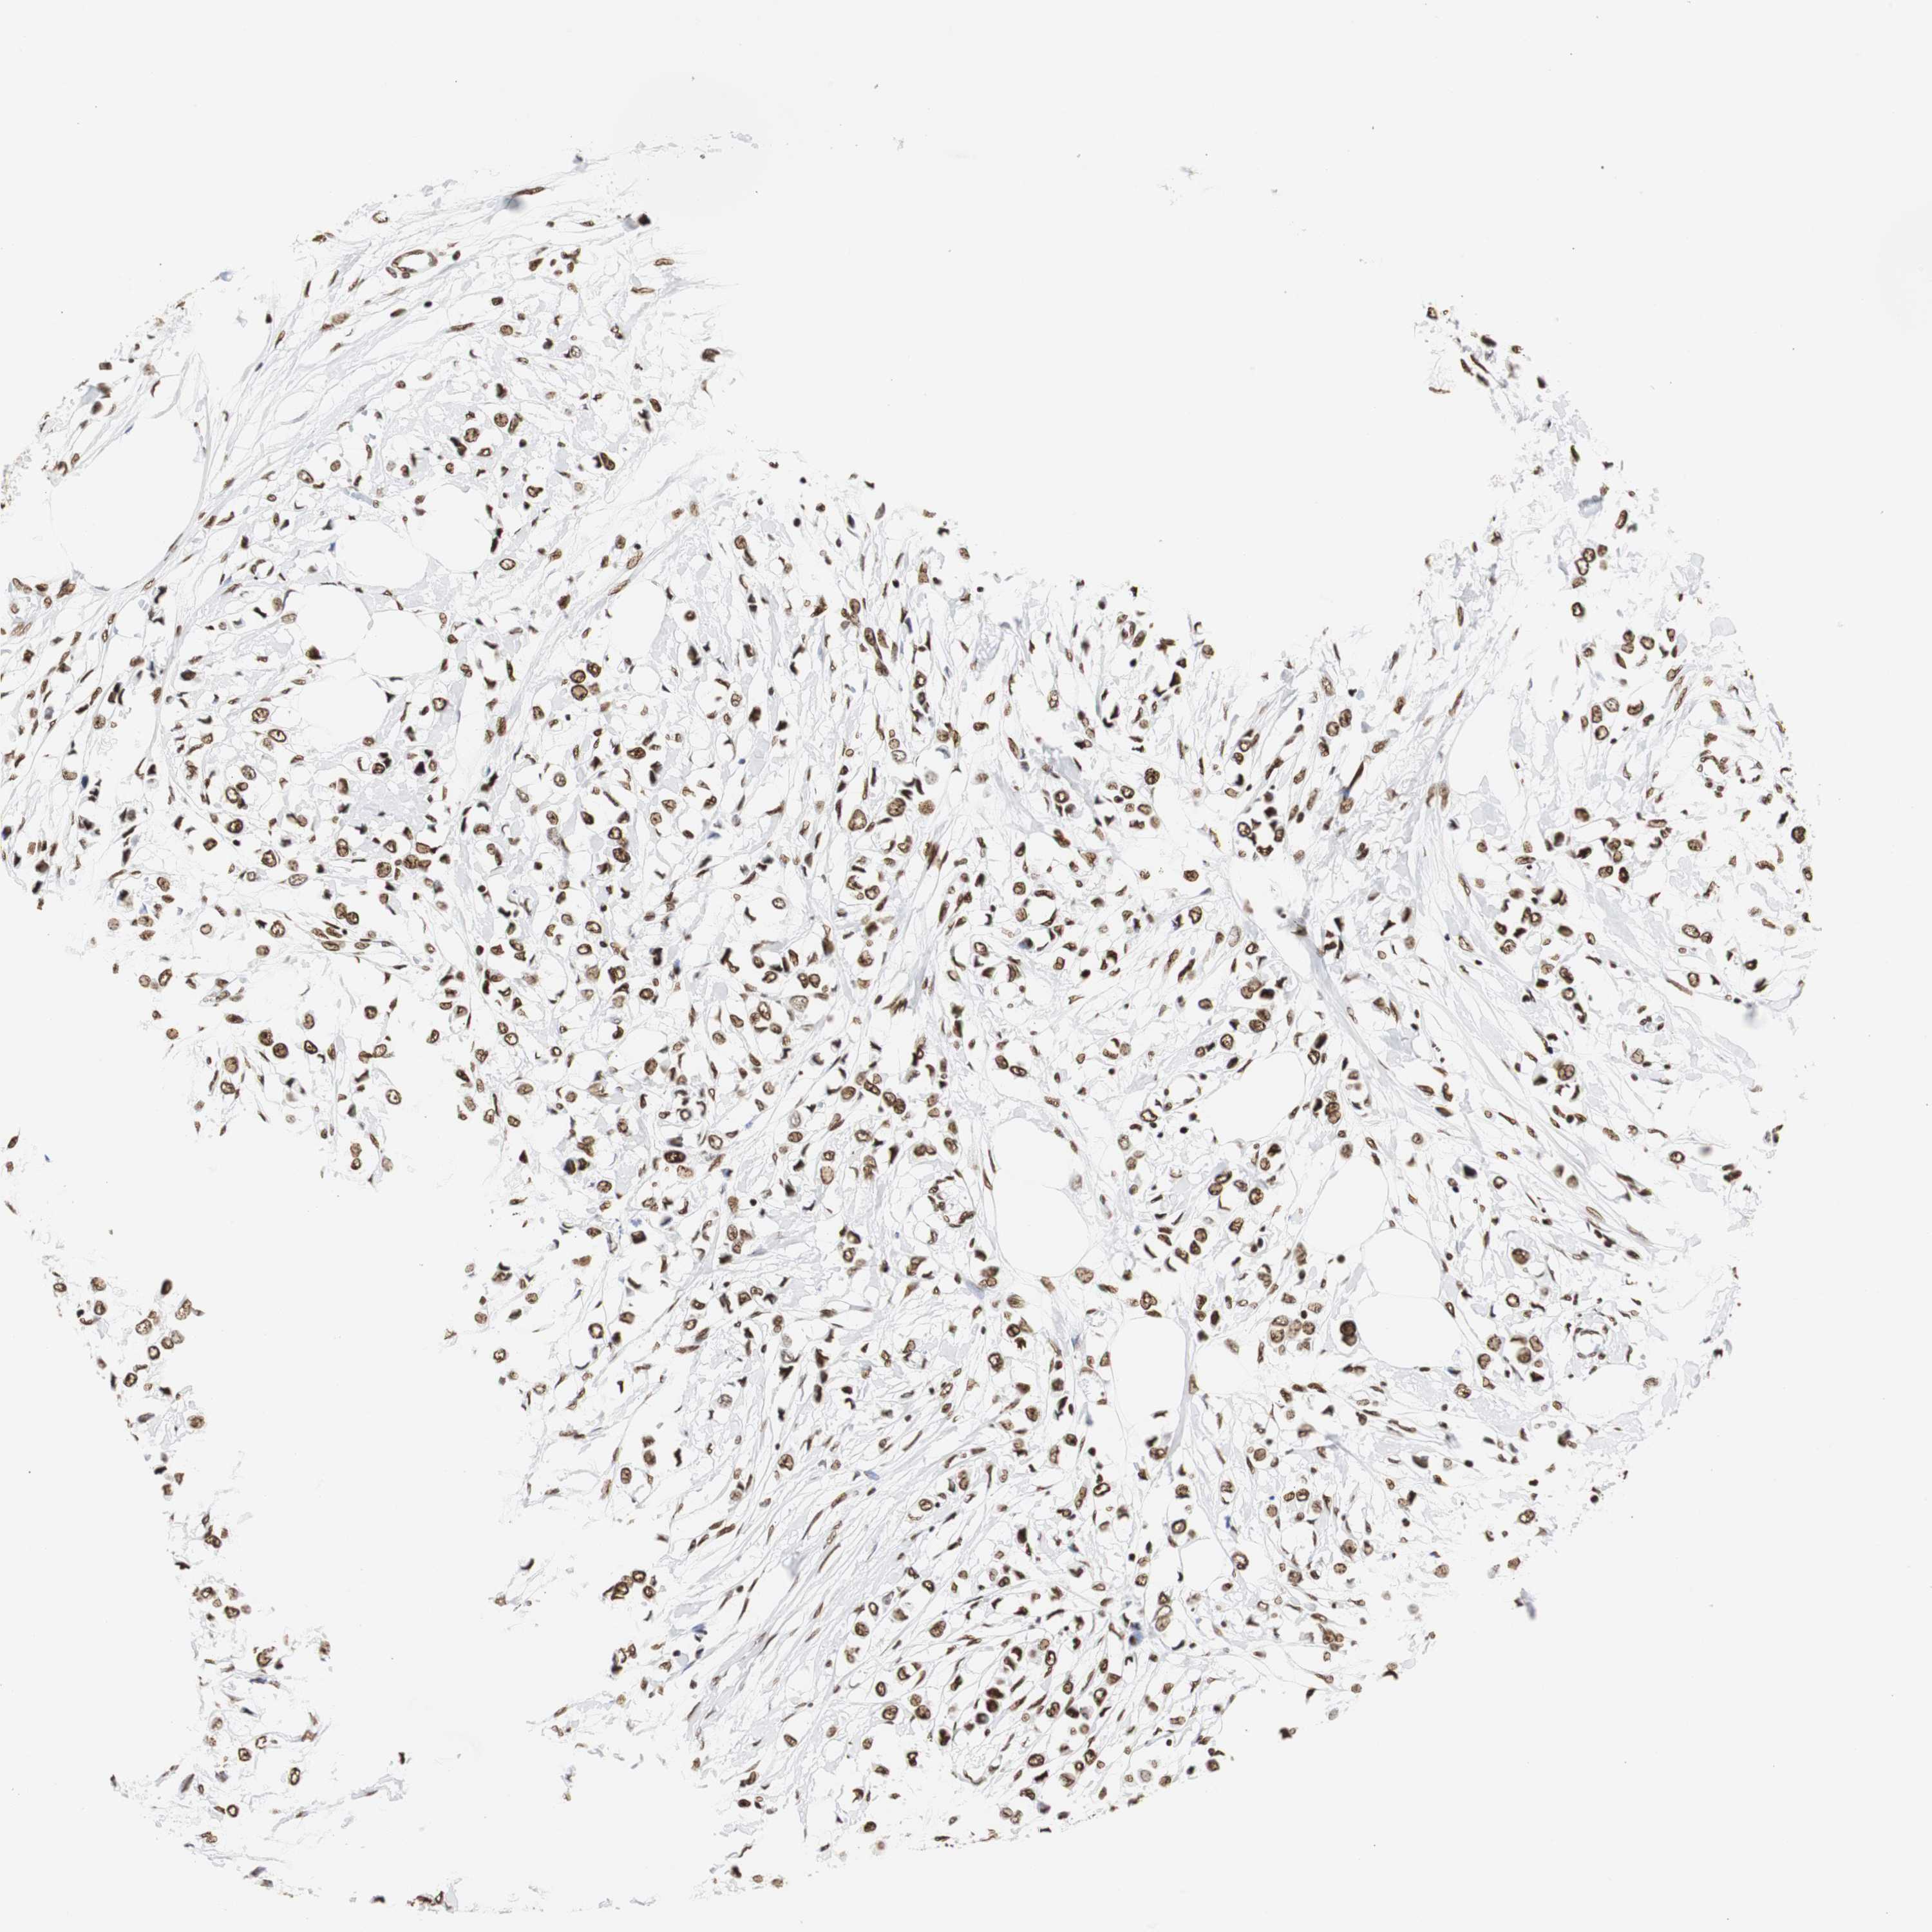

BRCA TCGA BRCA VALIDATION PROTEIN EXPRESSION